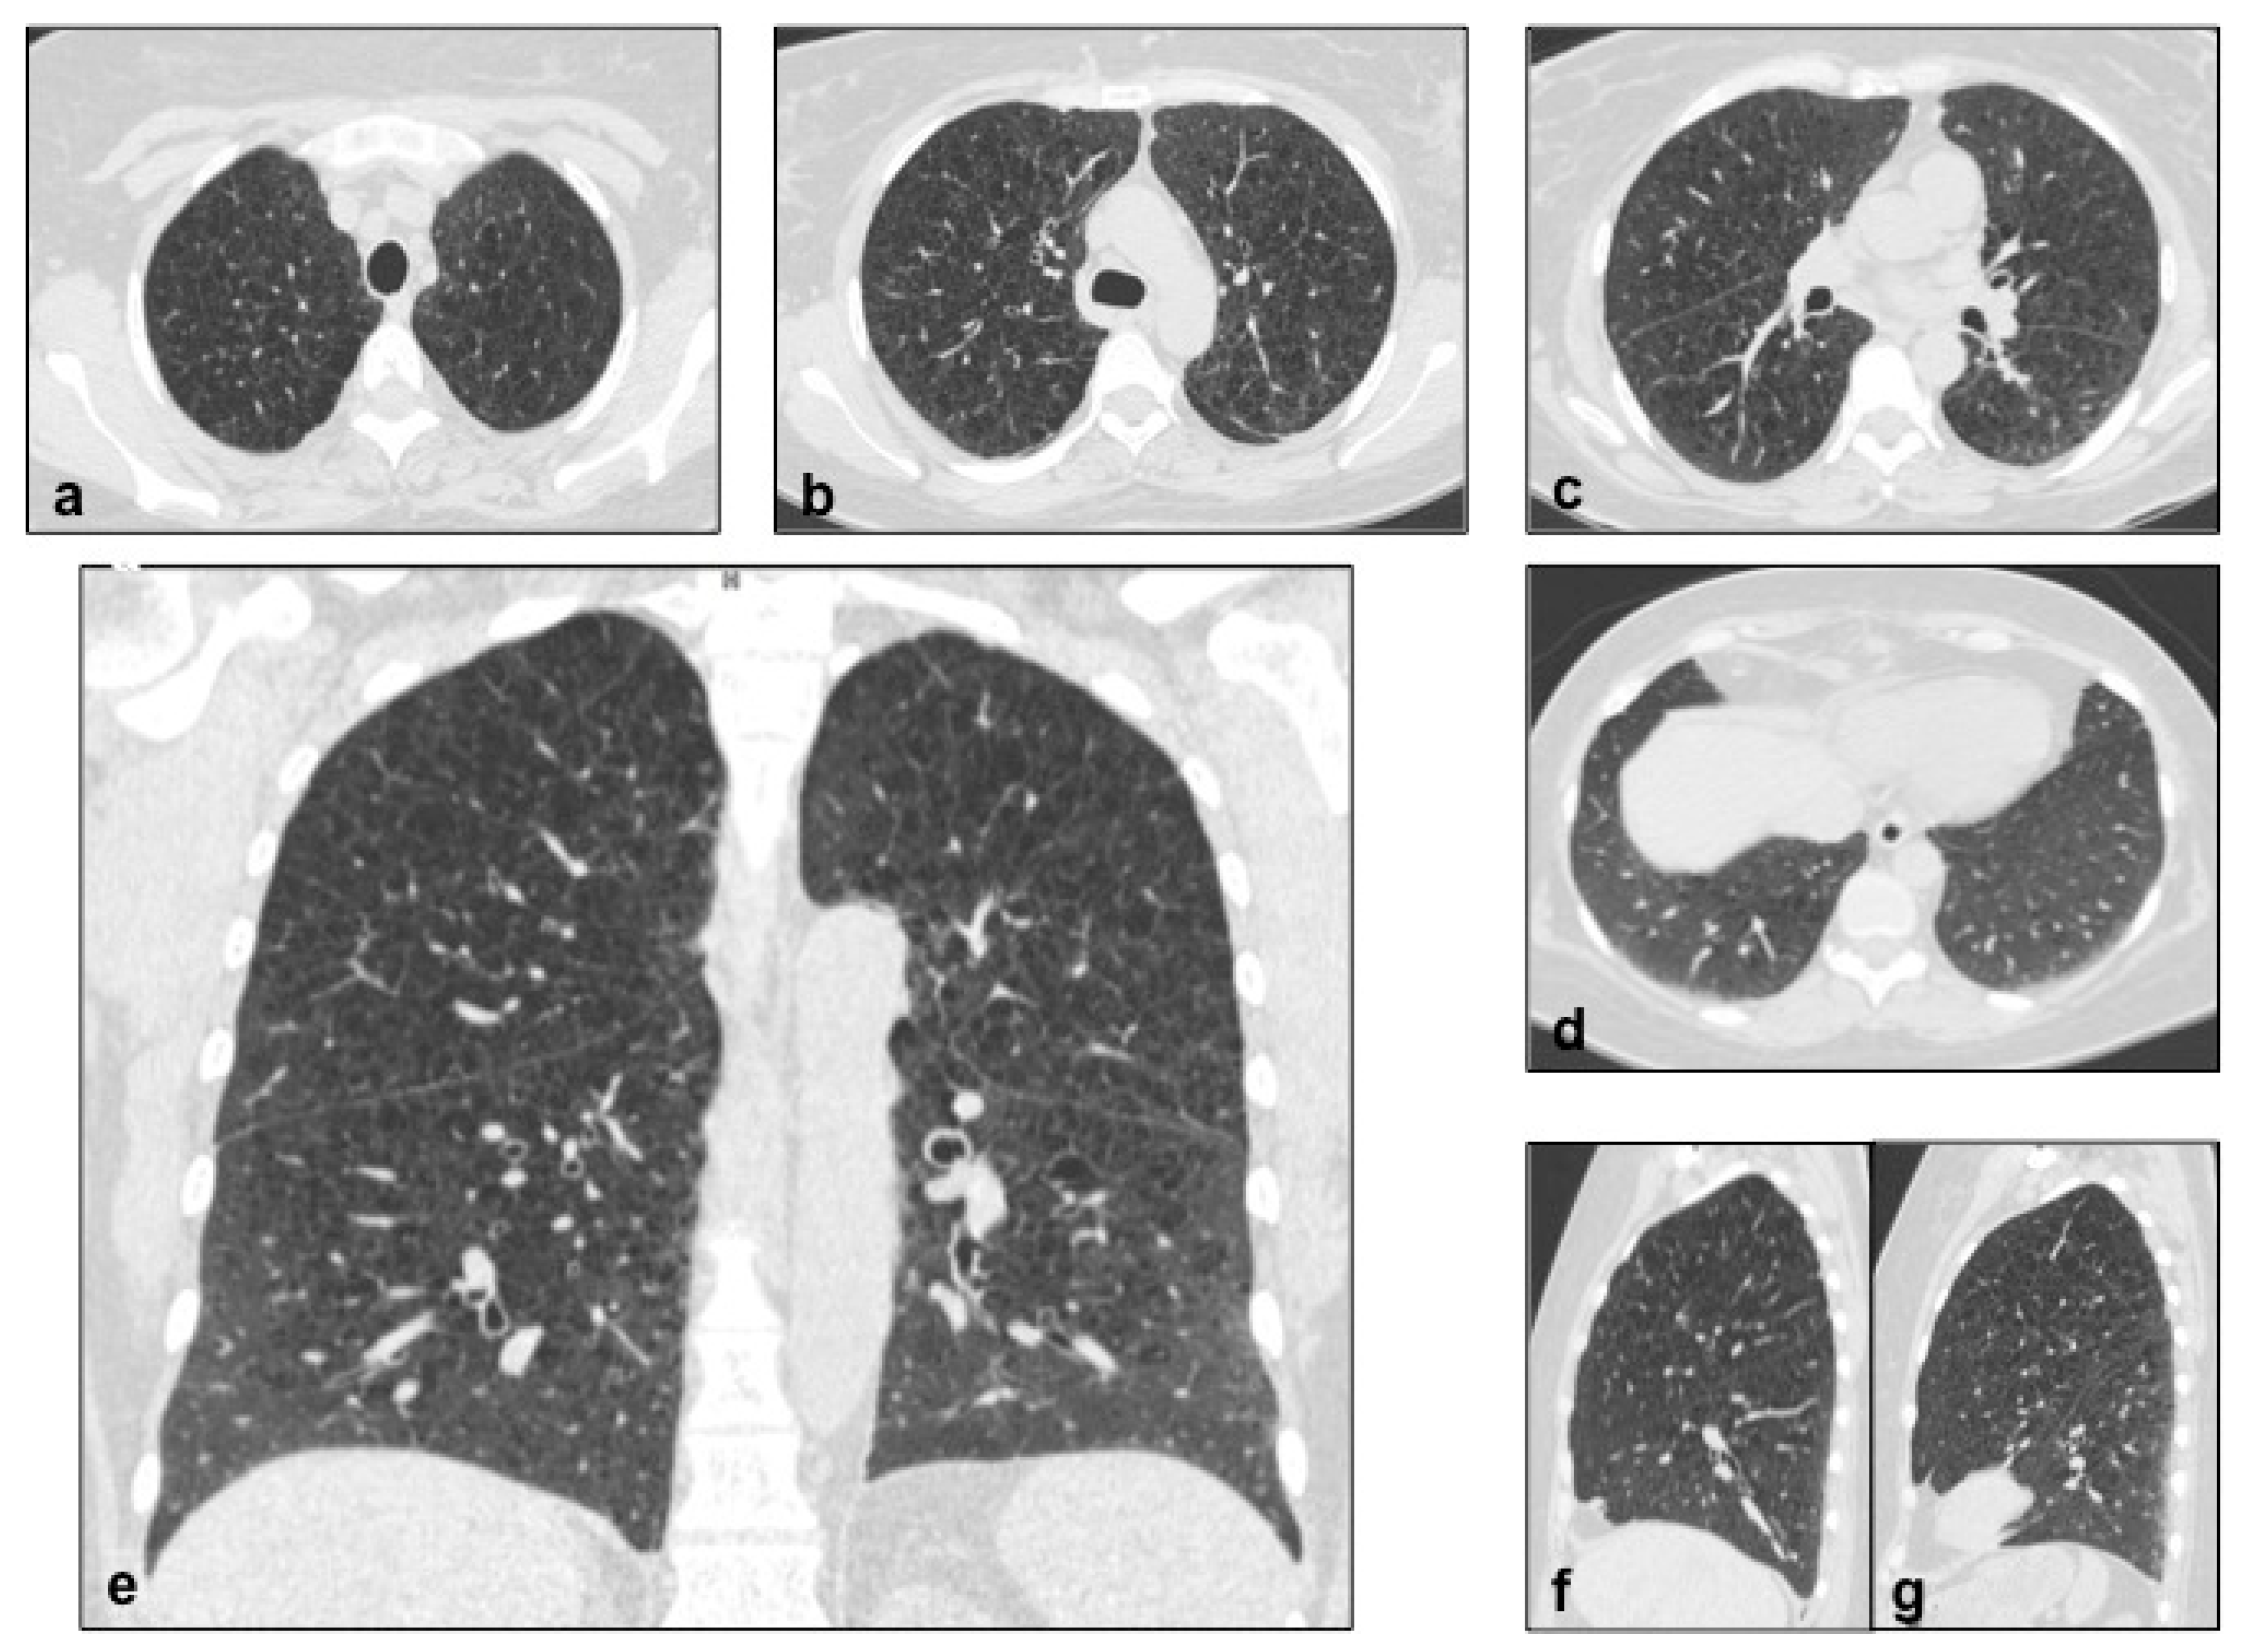

Figure 13. NF1 cysts are diffused and irregularly shaped, with no clearly-defined walls, mainly located in the upper lobes, symmetrically (ad). In addition to cysts, ground-glass opacities and emphysema are detected in this case. Multiplanar reconstruction (MPR) in the coronal (e) and sagittal (f,g) planes.

On chest radiographs, a reticular pattern with Kerley’s B lines may be observed in 50% of cases, associated with a typical lung volume increase; on HRCT scans, diffused and irregular shaped lung cysts or bullae can be rarely appreciated, predominantly distributed in upper lobes (Figure 12 and Figure 13), having symmetric location, with a significant risk of pneumothorax [46]; in addition to cysts, basilar bilateral reticulation, “ground glass” opacities and emphysema are often detected in these patients. Other thoracic alterations include cutaneous, subcutaneous and intercostal neurofibromas, “ribbon” ribs, thoracic meningoceles, paraganglioma, pheochromocytoma, intestinal carcinoids, mediastinal masses and pulmonary fibrosis [47].